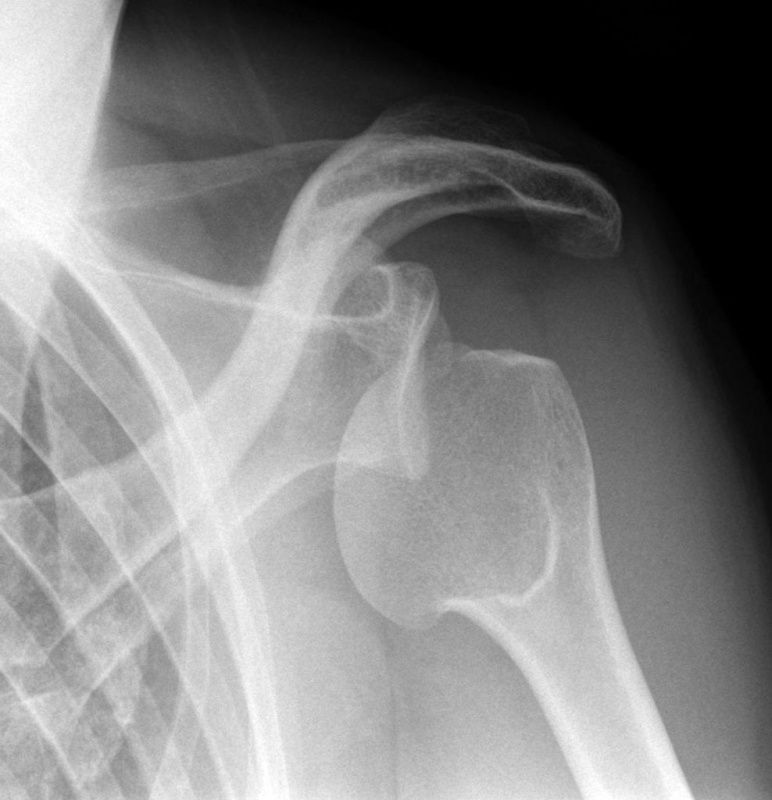

ПІСЛЯ АВТОМОБІЛЬНОЇ АВАРІЇ НА РЕНТГЕНОГРАМІ ВИЯВЛЕНО ПЕРЕЛОМ КІСТКИ В ДІЛЯНЦІ ХІРУРГІЧНОЇ ШИЙКИ. ЯКА КІСТКА МАЄ ТАКУ ШИЙКУ?

варіанти відповідей

ГОЛОВКИ HUMERUS

ДИСТАЛЬНОГО ЕПІФІЗА HUMERUS

ШИЙКИ FEMUR

ГОЛОВКИ FEMUR

ГОЛОВКИ RADIUS

ПРОКСИМАЛЬНОГО ЕПІФІЗА HUMERUS

ХІРУРГІЧНОЇ ШИЙКИ HUMERUS

АНАТОМІЧНОЇ ШИЙКИ HUMERUS